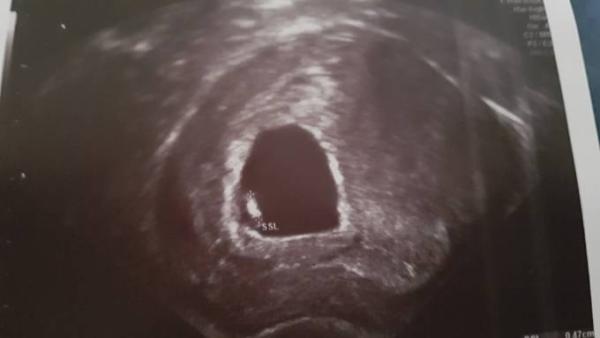

Als junimama 2018, darf ich mich nun zu euch gesellen. Ich bin laut Doc in der 8. SSW. Leider habe ich ein großes hämatom und die frauenärztin hat drohender abort in ihre Notizen geschrieben. Das Herz schlug jedoch schon mal. Trotzdem ist die Angst groß. Ist Nummer 3. Ich habe 2 Jungs. Einmal Dezember 2011 Und Mai 2018. Ich müsste lügen, wenn ich sagen würden, dass ich mir kein Mädchen wünsche

Bild zu vorsichtig anklopf - Forum für Januar - Mamis